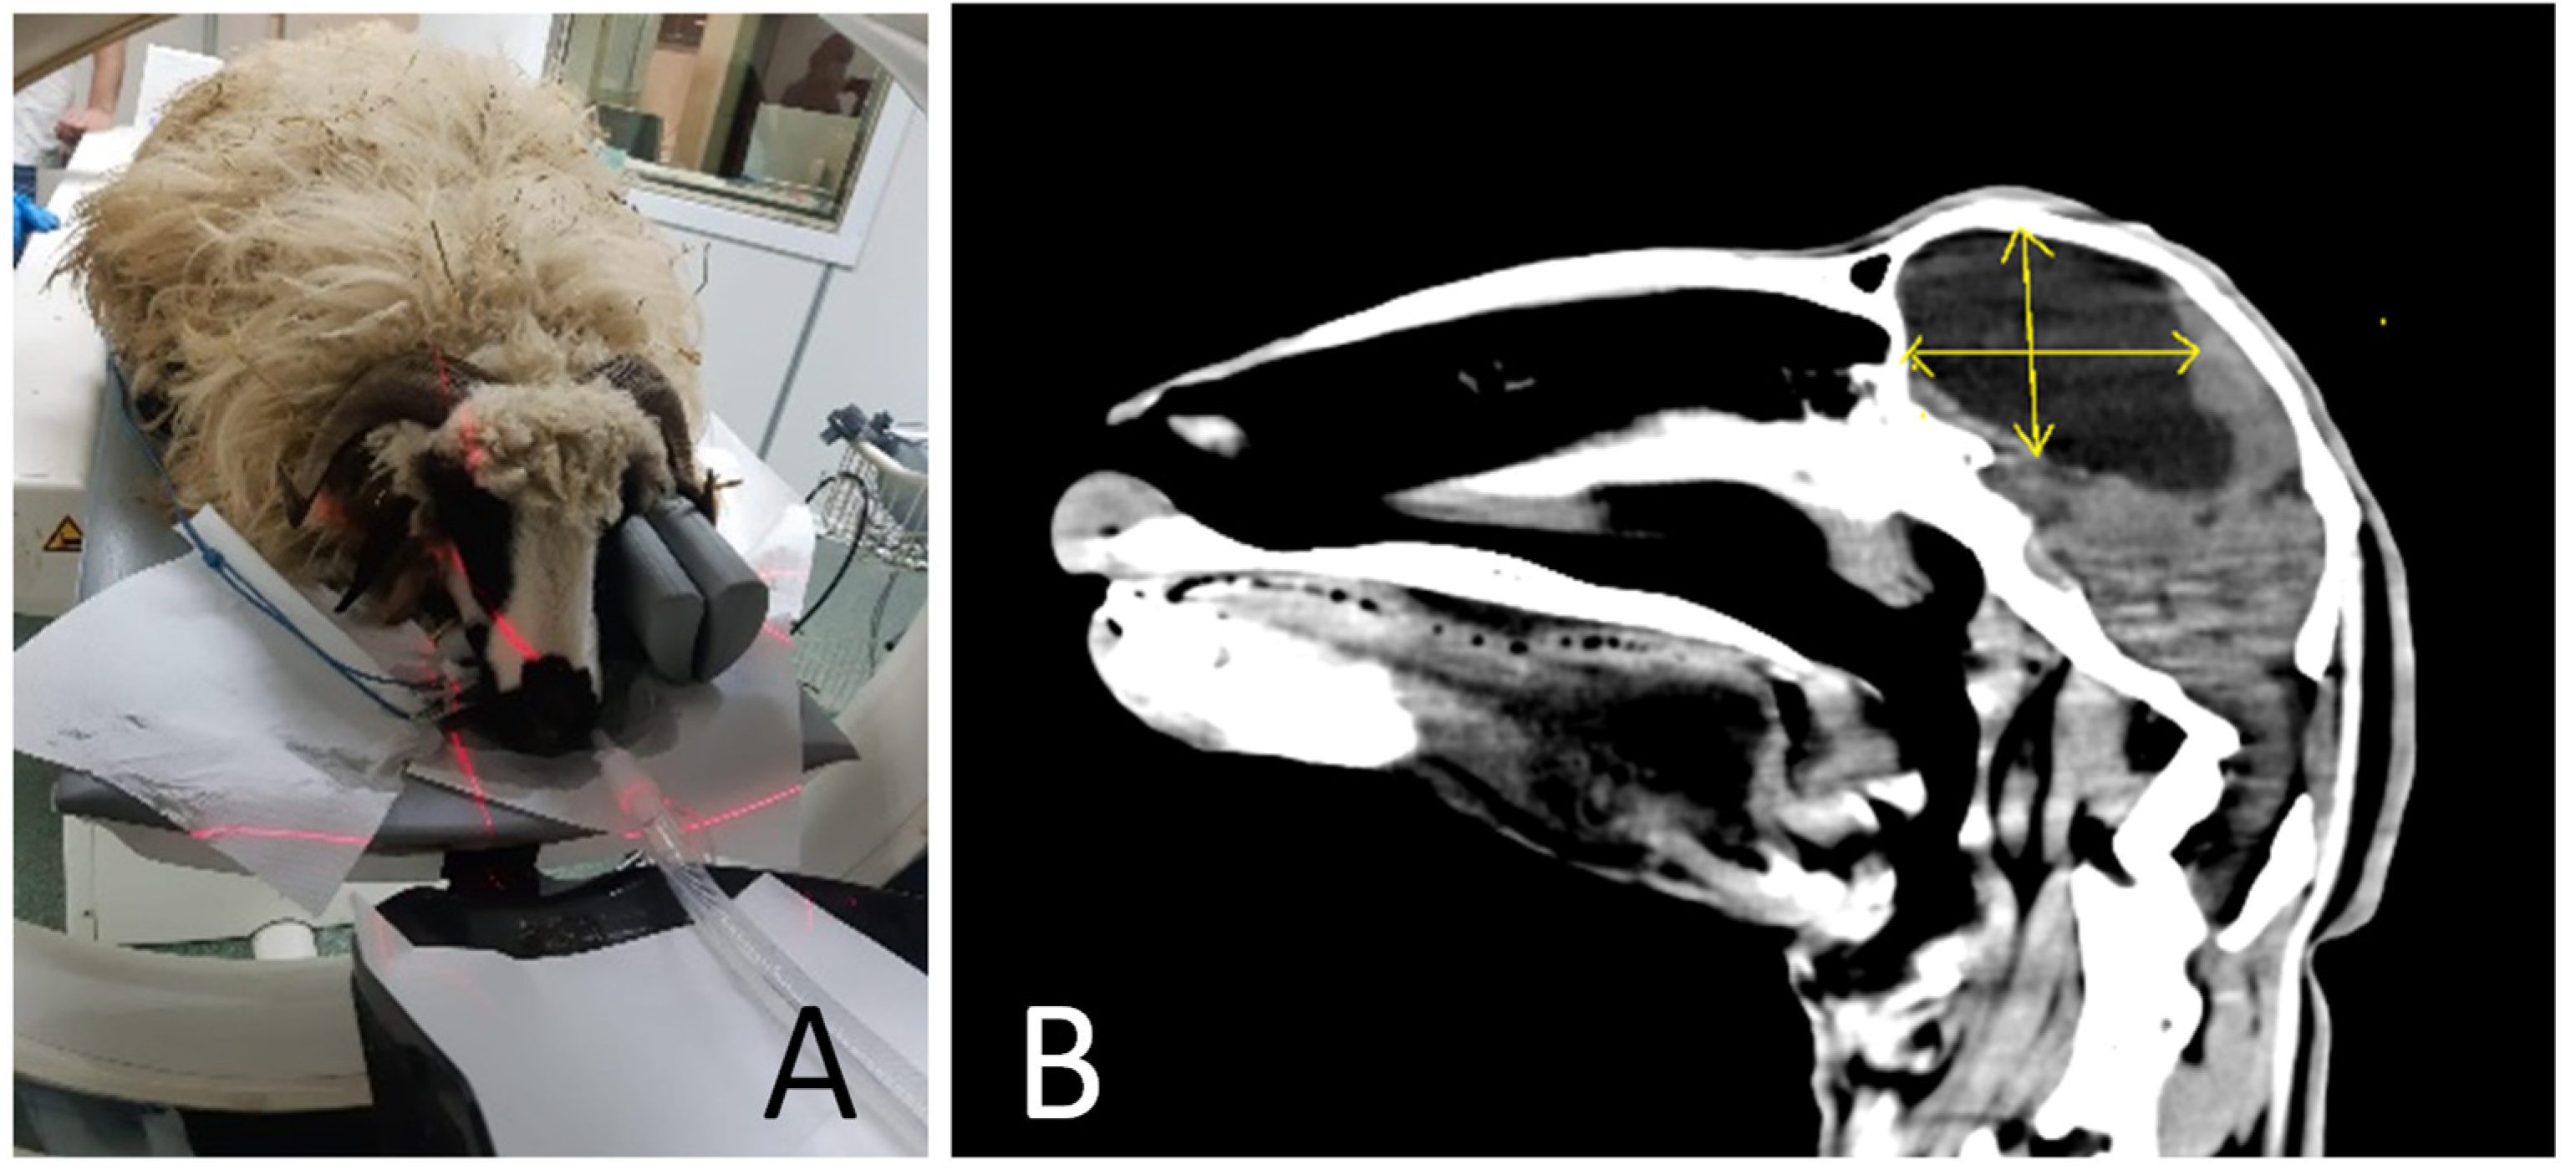

2.3. Computed Tomography (CT)

3.2. CT